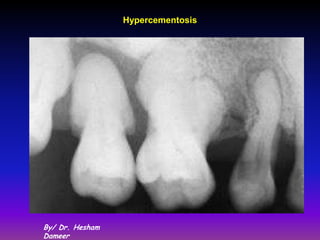

1) Hypercementosis:

It is an abnormal thickening of cementum, may be diffuse

or circumscribed.

It may affect all teeth of the dentition, be confined to a

single tooth, or even affect only Parts of one tooth.

If the overgrowth occurs in functional teeth and improves

the functional qualities of the cementum, it is termed

cementum hypertrophy.

If the overgrowth occurs in nonfunctional teeth, it is

termed cementum hyperplasia .

Hyperplastic cementum covering the enamel drops termed

excementosis

Localized hypercementosis

Generalized hypercementosis

In Localized hypertrophy prong like

extension of cementum may be

formed. This condition

frequently is found in teeth that

are exposed to great stress

(ortho) (compensatory

cementum). This extension of

cementum provide a larger

surface area for the attaching

fibers; thus a firmer anchorage

of the tooth to the surrounding

alveolar bone is assured.